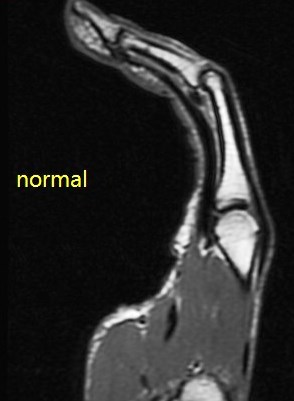

Figure 4 for case A2 pulley rupture finger (RID2437)

Figure 4

Imaging in flexion helps bring out this abnormality. The hand surgeon specifically requests it now. Also I ask the technologist to always include an adjacent normal finger for comparison.

A2 pulley rupture finger (RID2437)